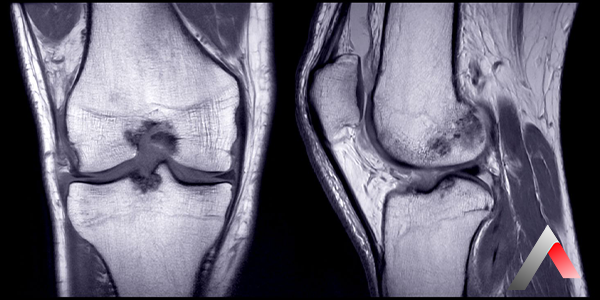

Diz eklemi, uyluk kemiği (femur) ile kaval kemiği (tibia) arasında yer alan kompleks bir yapıdır. Bu eklemin sağlıklı bir şekilde çalışması için, kemiklerin uçlarını kaplayan kıkırdak ve eklem boşluğunu dolduran sinovyal sıvı önemli bir rol oynar. Sinovyal sıvı, eklemi yağlayarak hareketleri kolaylaştırır, kıkırdakları besler ve darbeleri emer.

"Diz sıvı kaybı" terimi halk arasında sıkça kullanılsa da aslında eklemlerdeki sıvı miktarının azalması değil, sinoviyal sıvının yapısının bozulması ve işlevselliğini kaybetmesi söz konusudur. Bu durum, genellikle yaşlanma, aşırı kilo, yaralanmalar veya eklem hastalıkları (osteoartrit gibi) nedeniyle ortaya çıkar.

• Görüntüleme yöntemleri (röntgen, MR)